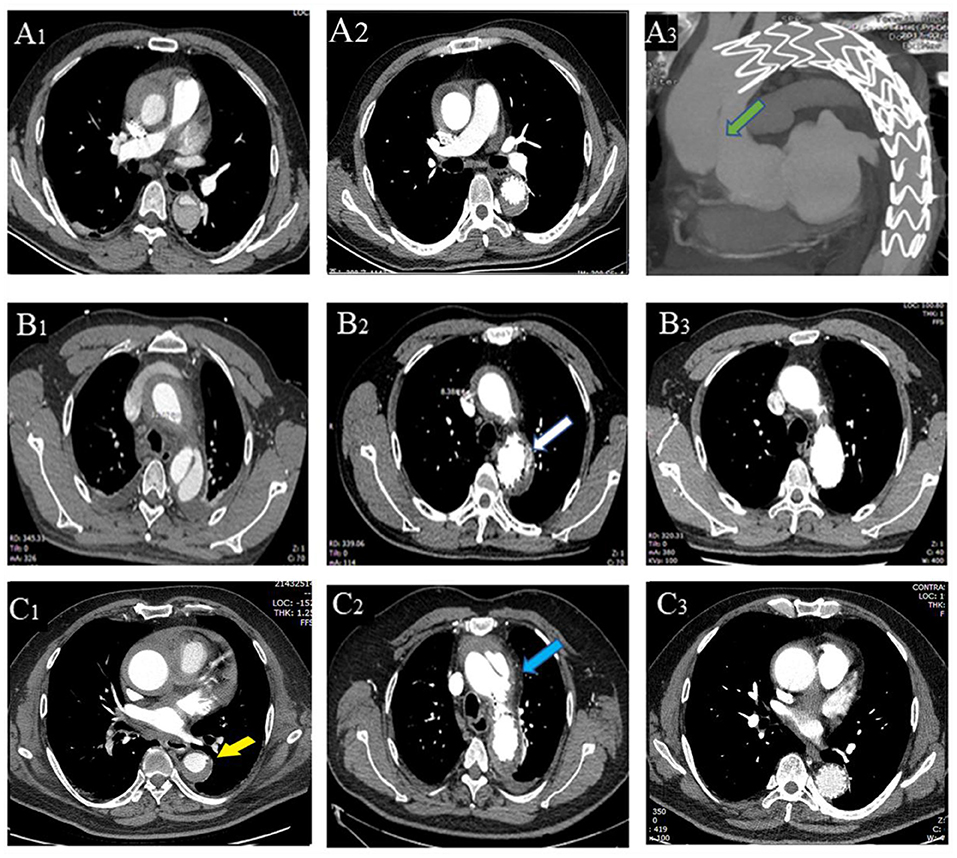

Contrast-enhanced computed tomography angiogram (CTA) was used to diagnose different entities and measure parameters. TAIMH is defined as hemorrhage consisting of a circular or crescentic thickening around the ascending aorta, and there is no blood flow between the lumen and the aortic wall (14). PAU is defined as an aortic atherosclerotic lesion in the internal elastic lamina that penetrates the media and is often accompanied by aortic calcification plaque (6, 14). Re-TAIMH was defined as TAIMH with PAU or entry tear in descending aorta (Figure 1). Meantime, the PAU will cause descending aortic hematoma, and the entry tear is a defect of the intimal flap in type B AD separating the true lumen (TL) and the false lumen (FL).

Figure 1. Contrast-enhanced computed tomography angiography (CTA) of the patients with retrograde type A aortic intramural hematoma (TAIMH). A patient with entry tear (green arrow) in descending aorta was treated by thoracic endovascular aortic repair (TEVAR), and the image was collected at admission (A1), 2 weeks after TEVAR (A2), and 3 months after TEVAR (A3,4), respectively. Another patient with penetrating atherosclerotic ulcer (PAU, blue arrow) and calcification plaque (white arrow) at admission (B1−3) and 2 weeks after TEVAR (B4), respectively. Intraoperative angiography of the two patients with retrograde TAIMH before (C1, entry tear, green arrow; C3, PAU, blue arrow) and after implanting stent grafts (C2, entry tear was blocked; C4, PAU was blocked).

At the first reexamination 14 days after TEVAR, one patient in Group A had type I endoleak (Figure 2). In Group B, one patient had aortic arch dissection induced by the proximal portion of stent graft and enlargement in MAAHT and MAAD (Figure 2), one had type I endoleak, and one had MAAHT and MAAD enlargement. All these patients chose to receive medical treatment and were alive, and changes in these complications during follow-up are shown in Table 4.

Figure 2. Thoracic endovascular aortic repair (TEVAR)-related complications. A patient with entry tear on admission (A1), 2 weeks after TEVAR (A2), and had type A aortic dissection 4 months (A3) after TEVAR (new entry tear in ascending aorta, green arrow). (B1–3) A patient with entry tear had type I endoleak (B2, white arrow) 2 weeks after TEVAR, which disappeared 6 months later (B3). A patient with penetrating atherosclerotic ulcer (PAU, yellow arrow, C1) had aortic arch dissection (blue arrow, C2) induced by proximal portion of stent graft with hematoma thickening 2 weeks after TEVAR, and the dissection was confined within the aortic arch with hematoma disappearing (C3).

After discharge, there were two deaths in each group (Table 4). One patient in Group A died of progression to type A AD and rupture 4 months after TEVAR and refused surgical treatment (Figure 2). Another one died of cerebral hemorrhage 6 years after TEVAR. In Group B, a patient developed type A AD and died of rupture on the way to referral, and another one encountered sudden death 2.7 years after TEVAR. In Group A, two patients had type I endoleak after discharge, and one patient was treated by endovascular repair of abdominal aortic dissection with pseudoaneurysm (Table 4).